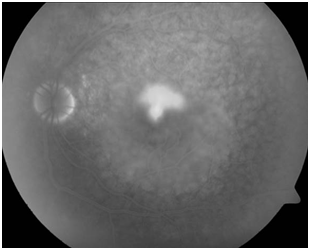

Figure 2C FA of right eye shows disseminated spotted choroidal hyper fluorescence and choroidal hypo fluorescence in macular area.

Figure 2D FA of left eye shows subtle hypo and hyper fluorescent areas.

Caucasian woman aged 22 who attends derived from another center with a diagnosis of unilateral CRCS after abruptly presented severe decrease in visual acuity (VA) in her left eye.Do not have a personal or family history of interest. The picture is not accompanied by systemic signs or symptoms. On examination, VA is 20/20 in her right eye and counting fingers in her left. The IOP is normal in both eyes. The anterior segment examination shows no signs of inflammation. The fundus examination shows a brightening of the internal limiting membrane in the posterior pole of both eyes and a macular neurosensory detachment with a brownish hue in the left eye (Figure 2A&2B). The FA shows hyper fluorescent macular lesion in the right eye with multiple hyper fluorescent spots inside, taking a look of “starry night”, and hyper fluorescence of the optic disc in both eyes (Figure 2C&2D). The OCT of the right eye shows large loculated neurosensory detachment in the macular area. The OCT of the left eye shows neurosensory detachment (Figure 2E& 2F).